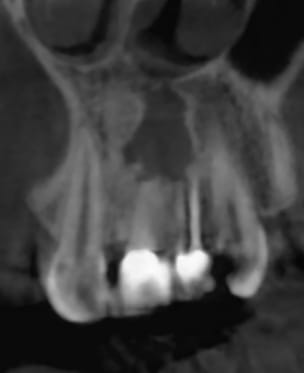

Patiente de 23 ans à peine.

La résection a été faite 1 an plus tôt...

Elle consulte pour remplacer toutes les dents manquantes, réparer toutes celles qui faut réparer, mais surtout pour son sourire qui la complexe à cause de la 21 et 22 (couronne céramo-métallique moche, couleur plus saturée que la 11 et 12, métal visible, coloration violette de la gencive...), grande cicatrice au niveau péri apicale avec fistule et un peu de pus à la pression, absence d'os à laquelle il faudrait remédier...

Pas de douleur. Pas de mobilité.

Je rajoutes quelques coupes et une rétro... C'est vraiment un massacre à la tronçonneuse!